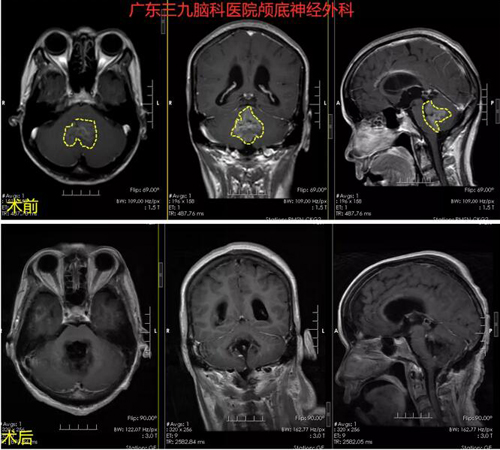

神经外一科主任张良接诊了林某。在详细了解病情后,建议做头部MRI增强检查,待结果回报后再做下一步治疗。检查结果显示:左侧颞底脑膜瘤,局部脑水肿明显,毗邻乙状窦、横窦。张良主任指出,如果肿瘤进一步长大,将大大增大手术风险,建议马上实施手术治疗。在与林某及其家人商量后,同意手术治疗。

完善术前检查后,由张良主任主刀在全麻下为林某行“左侧颞底脑膜瘤切除术”,术程顺利,病理报告示:(左侧颞底)脑膜皮细胞型脑膜瘤WHO I级。

▲术前MR 1.左侧颞底占位性病变,考虑小脑膜瘤;2.脑白质散在变性灶;3.双侧额顶叶局限性脑萎缩;4.脑MRV检查未见异常。

术后MR示术后改变,肿瘤原病变已切除。

▲术后病理:(左侧颞部)脑膜皮细胞型脑膜瘤WHO I级